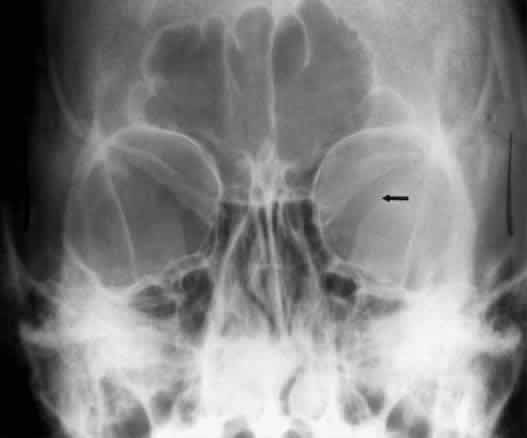

The superior orbital fissure has interpersonal and intrapersonal variations. The fissure should be symmetric, but there is no good measurement that identifies pathology, other than marked asymmetry. The fissure can be enlarged by infraclinoid aneurysm, carotid-cavernous fistulas, pituitary tumors, and meningiomas.26 Less common causes for enlargement include hemangiomas, lymphoma, mucocele of the sphenoid sinus, and neurofibromatosis (Fig. 15).

Fig. 15. Enlargement of the left superior orbital fissure (arrow) by neurofibromatosis. The Caldwell projection gives the best view of this fissure.